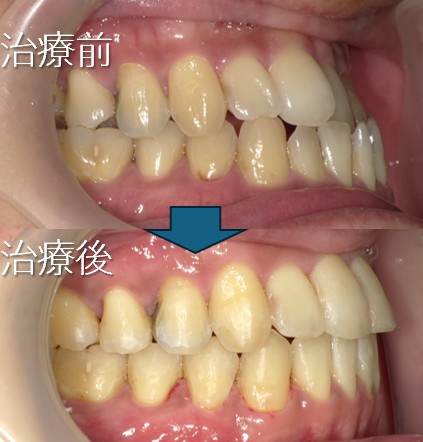

上の歯が前に出ている(上顎前突:いわゆる出っ歯など)

上顎前突:出っ歯

・主訴:出っ歯である

・診断:上顎前突

・年齢:20歳

・使用した主な装置:マルチブラケット装置

・抜歯部位:第一小臼歯を4本抜去

・治療期間:24か月

・通院回数:24回

・費用の目安:矯正料金として60万+税金。診断料金6.5円+税金。

調整処置料金:月3000円+税金を24回で7万2千円+税金。 第一小臼歯を4本抜去:1本5千円+税金。 総額 832.100円。

リスク・副作用:

・前歯の位置を修正するために、必要上、歯を減らします。

・虫歯にならない様に、通常の歯磨きを工夫することが必要です。

・歯が動く際に、歯のゆれを痛みとして感じることがあります。

・根の吸収が起きることがあります。

・保定をしないと後戻りが起きることがあります。